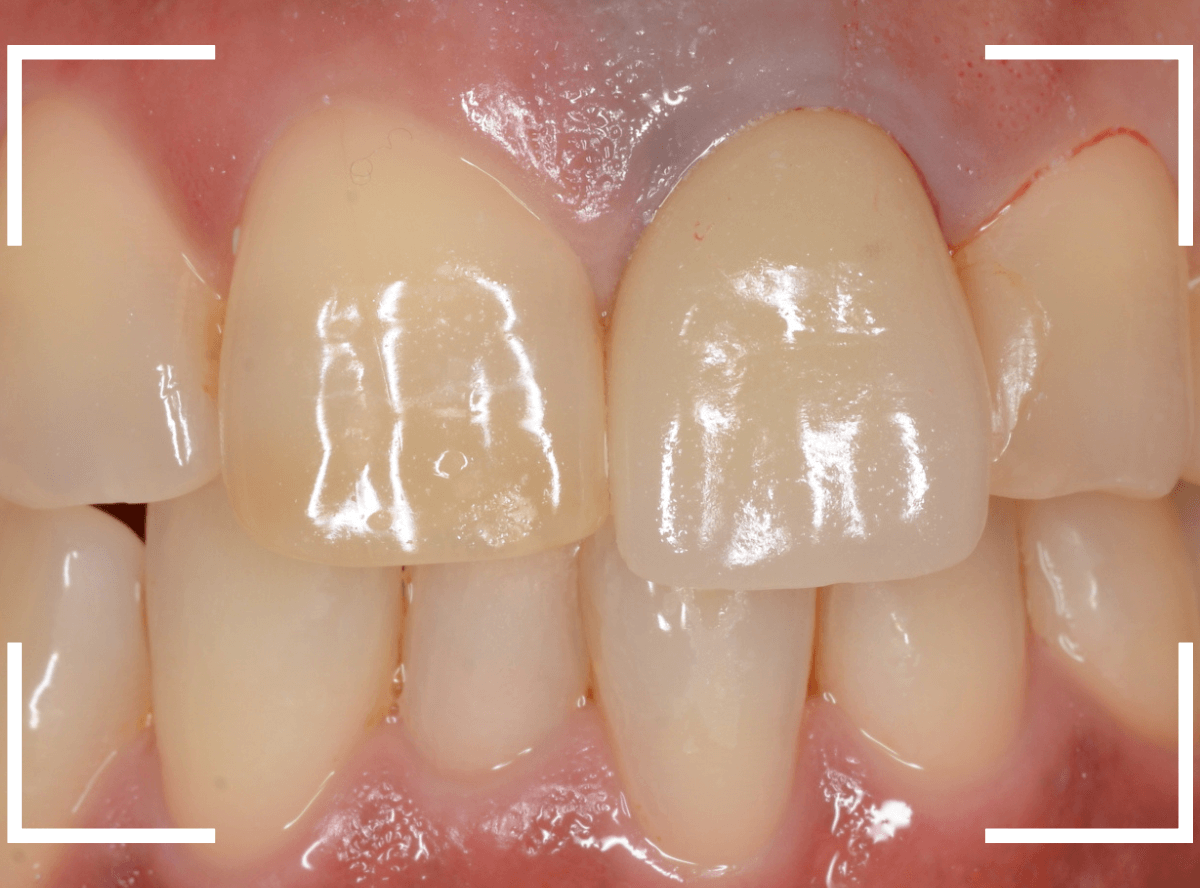

今回は、上の前歯のセラミックの形が気になるので、大分時間も経っているので新規に作り直したいというご希望の患者さんのお話です。

たしかに、隣の歯に比べてかなり下に下がってしまっています。

治療した時の状況がわからないので、治療時からどれくらい下がったのかは正確にはわかりません(><)

裏側を見ると少し歯肉が腫れています。

歯周病の治療と並行して、セラミックの作り直しをすることになりました。

治療前と治療後の比較、前から見たところです。